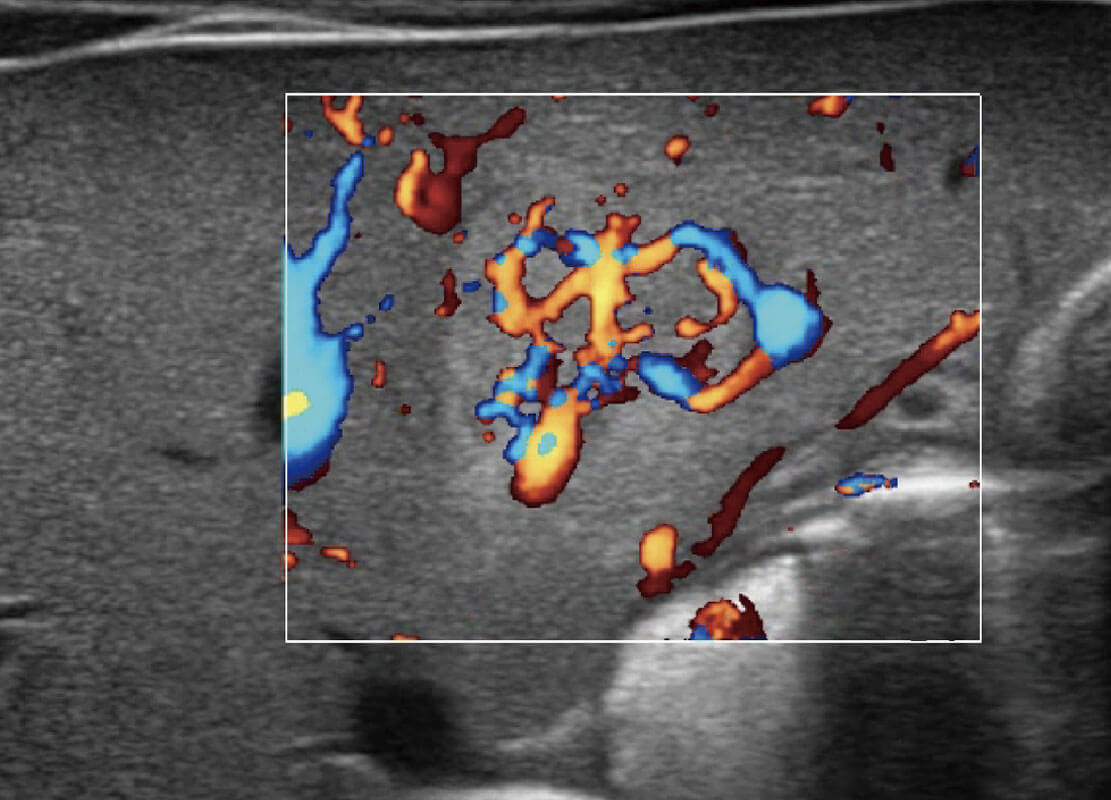

乳腺导管癌

乳腺癌显微血流